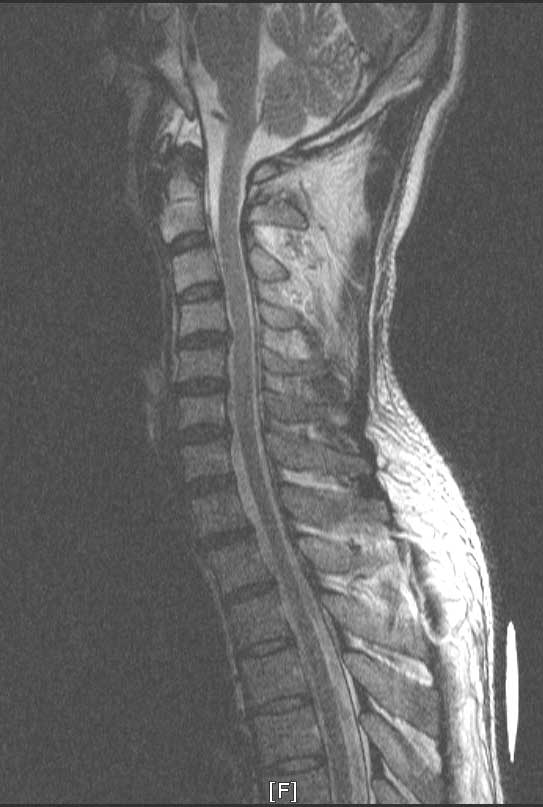

, ü Ư Ű 175 Cm ü 80 Kg 37 ȯ 1C.ڵ, 1C., 1C.ڵӸ , 1C.ٽŰ, 1C.ٸǷ, 1C., 1C.ھ, 1C.ٱ (), 1C.߷ (), 1C.Ƿ (), 1C.ٰ , 1C.ٳ 2C.ھȱ , 2C.ٴ, 2C., 2C,3C,ΰ 6C.ڸ , 6C. κ Ḳ , 6C.ھ Ḳ , 6C.ڻ , 6C.7C.ھ հ ̳ 7C.Ȳġ, 7C.ڿʰ , 1T.ڼյ չٴ , 1T.ڼո , 1T.ڼհ ü ̳ , 1T.Ȳġ, 1T. κ , 2T.ڼյ(κ) , 2T. Ʒκ 6T. Ű , 6T.ټ , 3L.ٹ̻, 3L.ڹ 5L.ڹ߸̳ , ()κп ̻ ܵ. ()ũ( ߰Ż), ǥغ Ͻô Ͽ ߰ մϴ. ũ(߰Ż), ũ(߰Ż)ġ, հ , , հ , ġ, , Ḳ , , Ḳ ġ Ǵ , , ȱ ǰϰų ڸ, , ڰ , , Ǵ ġ ʰ, װ Ǵ ġ ͳ õ ߰ Ż ( 5-6, 6-7) ҽϴ. Ÿ Ǿϴ (3~4 ) α ڷ ǻͷ ۾ Ϸ 10ð ̻ ߽ϴ. Ϸ ɾ ִ ð ü ϰ ʿ ΰ ϰ Ͽϴ. 10 4~5ȸ Ͽ ô 3 ã ް Ȱ 3 ݱ ġ ֻ絵 3 ҽϴ.(λ 츮 ) ǻ Ըδ 1ȸ ֻ縦 ´ٰ ߾µ 3 ¾Ƶ ʰ ° ҽϴ. Ͽ Ժη Į 뼱 ȵȴٰ ر ... 쳪 ٴϰ ϸ ƮĪϰ ִµ 쳪 ణ ־ ȴٴ ȵ ϴ. ΰ µ ũ ݽ ü Ⱦ ϴ. ü Ư ϰ ʴϴ. 1. : Ư α 2. : Ȳġ ~ յ հ 3. : Ư 4. : 5. ٸ : ߸ Ư ϰ ܿⰡ 鶧 ̻Դϴ. ϳ ٲμ ± ִٸ.. ϳ Ź帳ϴ. Ẹ ü Դϴ. ϼ |